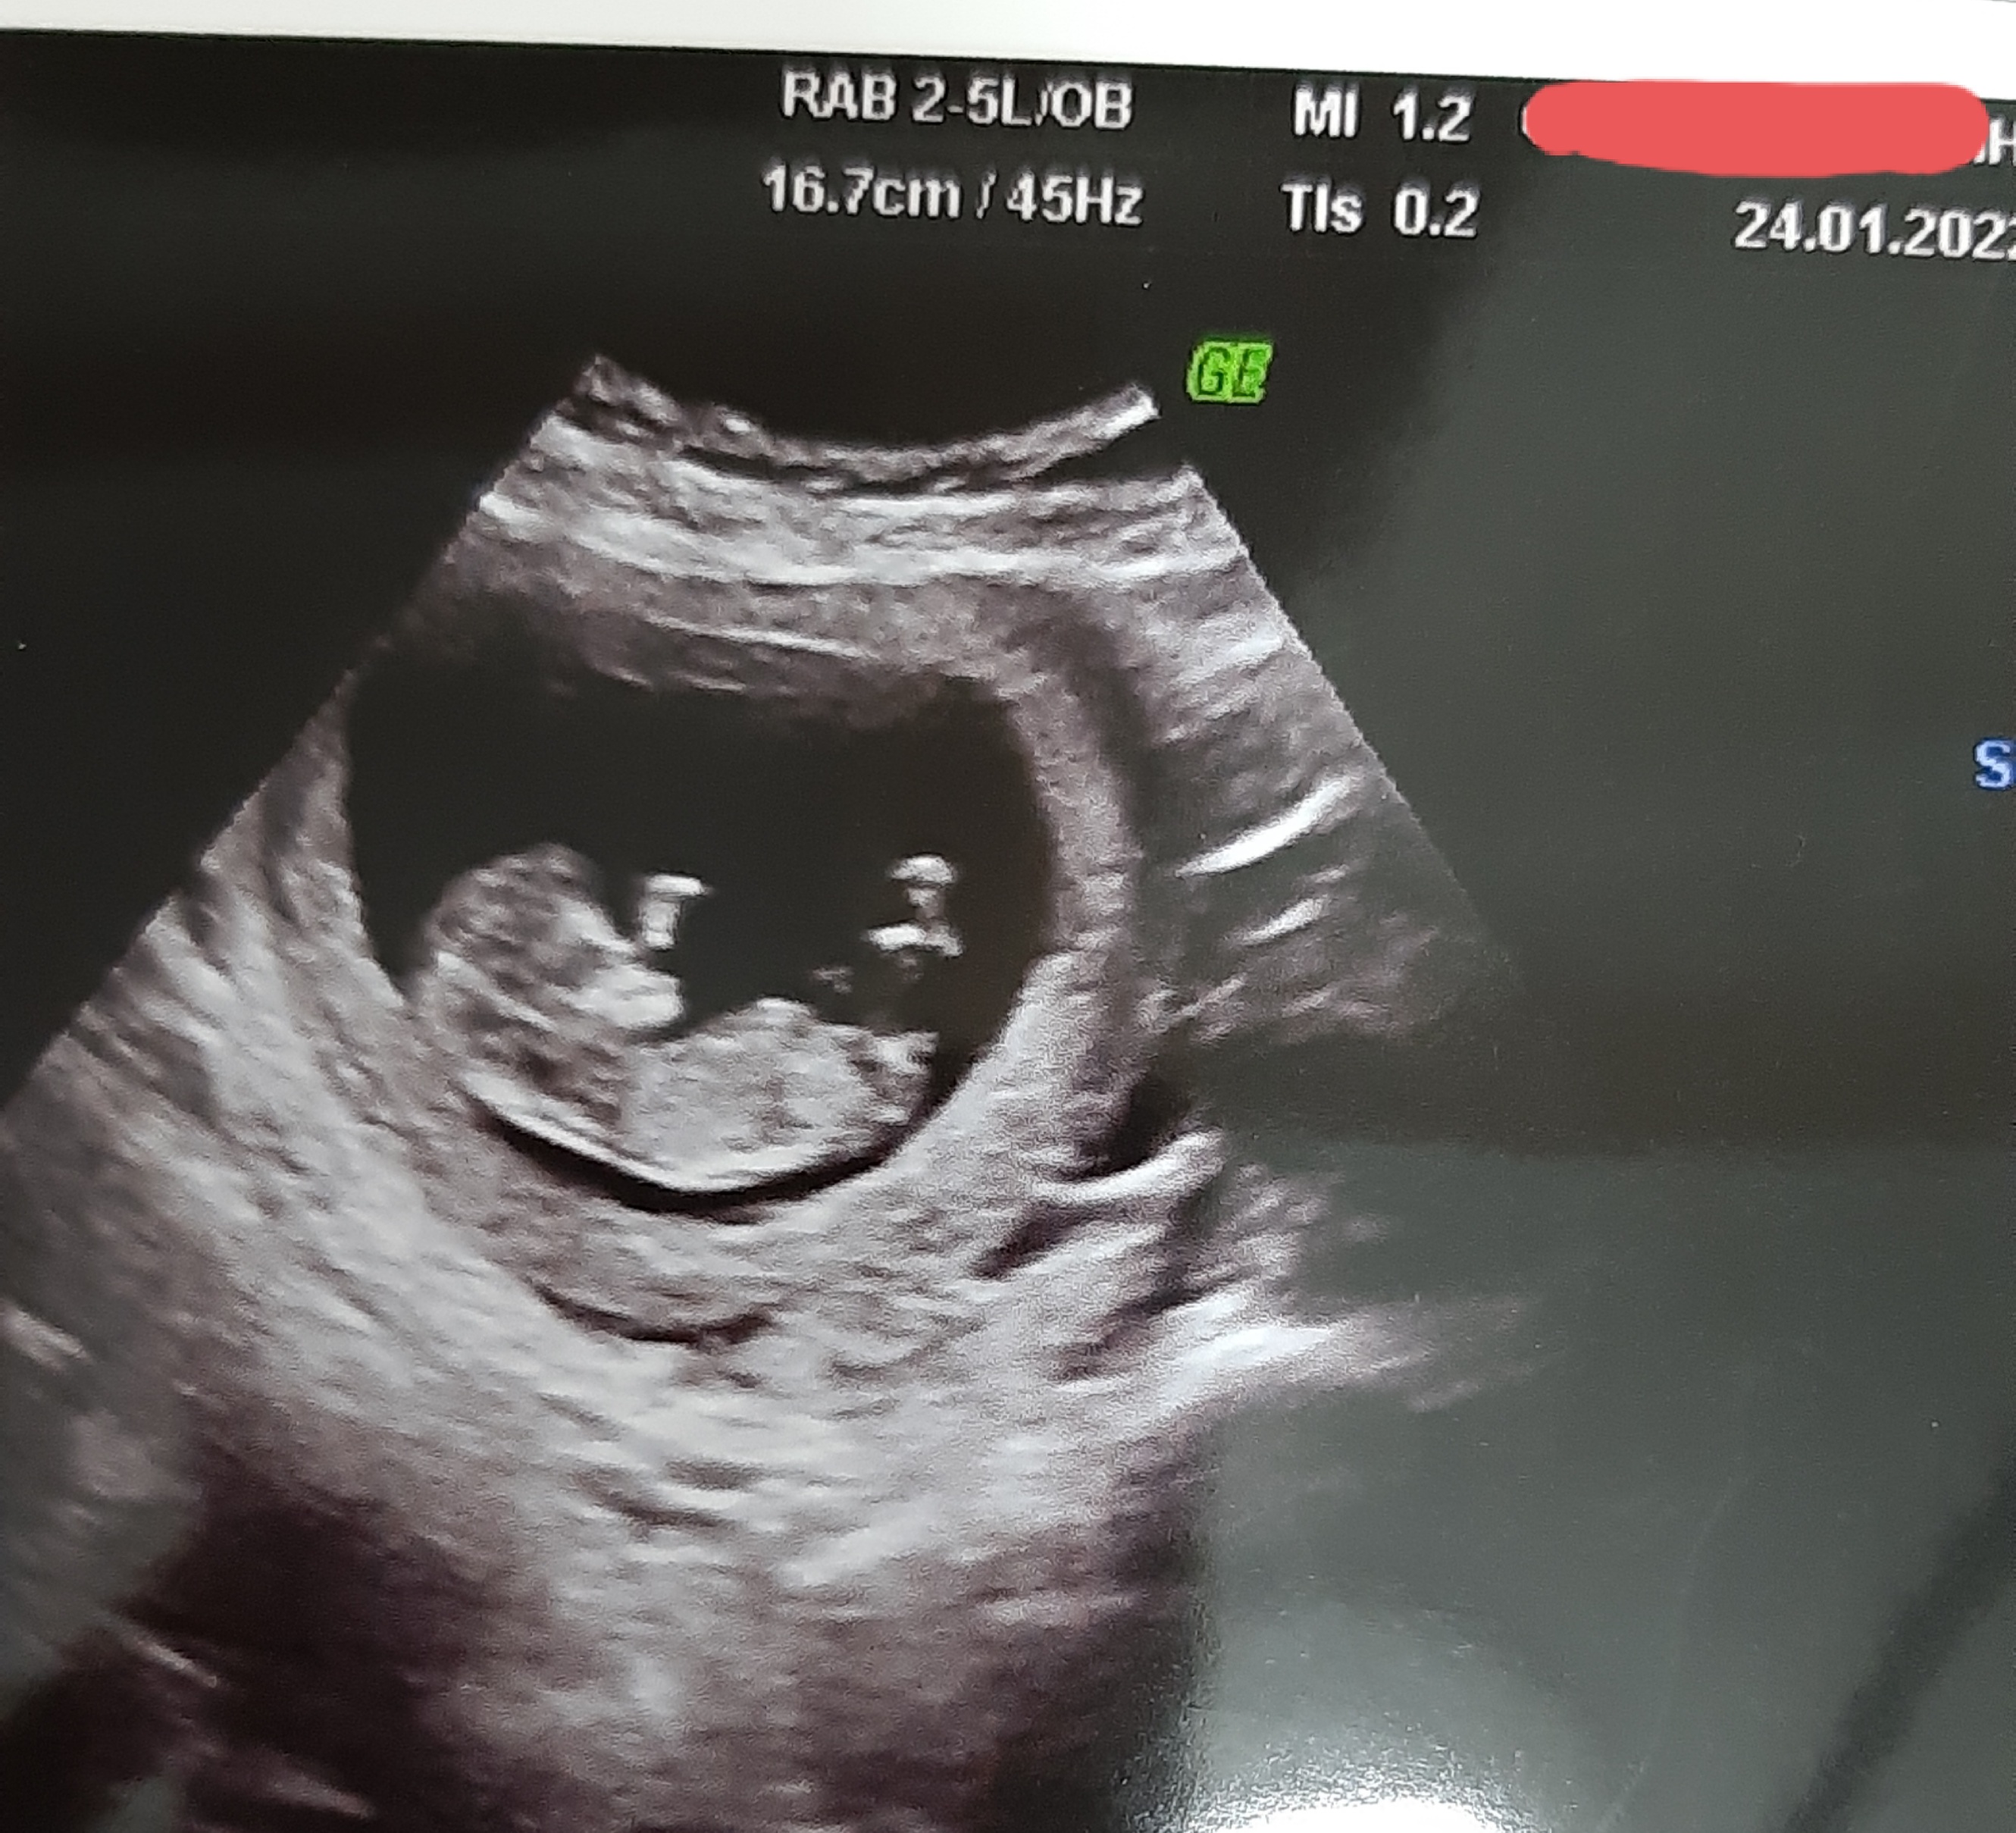

Kızlar Mrb sizce nub teorisine gire cinsiyet ne görünüyor

• 20220124_173446.jpg

1.2 MB · Görüntüleme: 546